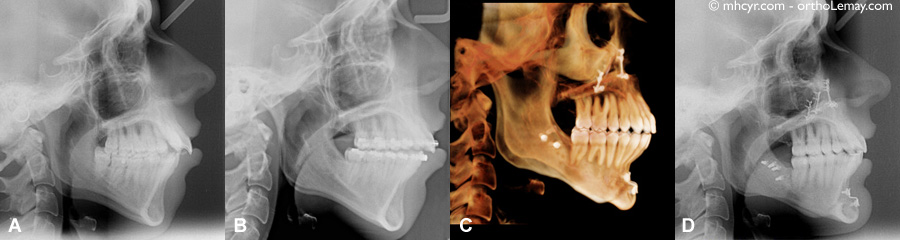

Radiographies céphalométriques

Radiographies céphalométriques; (A) Avant le traitement, (B) après la préparation orthodontique et avant la chirurgie, (C et D) après la fin du traitement. On peut clairement voir les plaques et vis de fixation rigides sur chaque mâchoire et sur le menton.